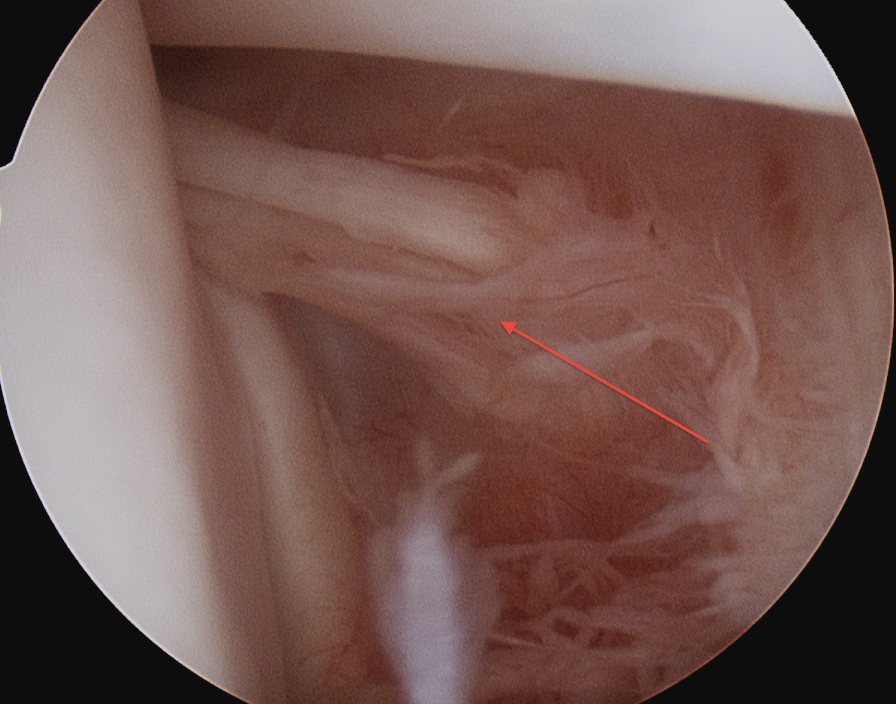

![]() |

| Inferior glenohumeral ligament (IGHL) | |

|

Origin: Inferior 2/3 glenoid and labrum Insertion: Anatomical neck humerus

Anterior band: antero-inferior glenoid to 3 o'clock Posterior band: postero-inferior glenoid to 9 o'clock Axillary pouch between two bands |

| Most important ligament in terms of stability | Stabilizes arm at 90 degrees of abduction |

Anterior IGHL glenoid attachment |

IGHL humeral attachment |

Inferior recess

Loose body in inferior recess